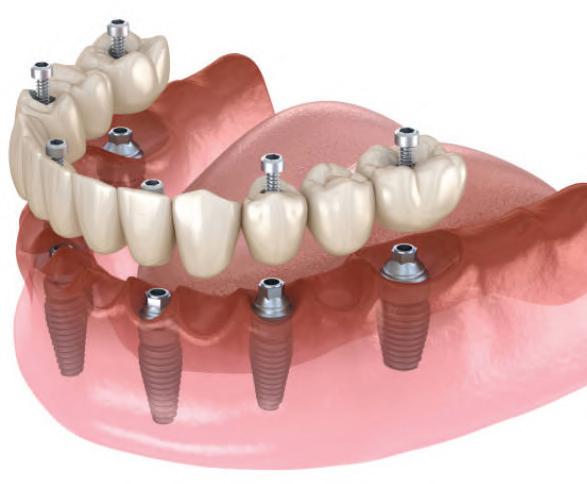

22 | Bariatric Surgery: Dr.’s Cover the Insurance Coverage Option | By Etwar McBean, MD, FACS 24 | All-On-Four Dental Implants | Submitted By Sivakumar Sreenivasan, DMD, MDS

Can just four implants replace all of the teeth on the top or the bottom of your mouth? Thanks to advances in dental implant technology, that answer is a resounding yes.

Tooth loss is extremely common among adults, especially as we age. Rather than living with the discomfort and hassles of dentures, many people are opting for what is called “all-onfour” dental implant restoration.

An implant is a small titanium

screw that fits inside your jawbone and replaces the root-part of a missing tooth. Minor surgery is required to insert the implants. Once the implant is in place, a crown is attached to give you a highly realistic-looking and functional prosthetic tooth.

You do not need a dental implant for each and every one of your missing teeth. All you need is four precisely placed implants on the top of your mouth, and four on the bottom, to restore your full smile. That’s the beauty of the all-on-four. And because the implant is made of titanium, it has the unique ability to fuse to living bone and function as part of it. So eventually, the dental implant becomes part of the jawbone and serves as a strong, longlasting foundation for your new teeth.

Besides ensuring that your implants are permanently fixed in place, this bone fusion has another important benefit: it prevents future bone loss in the jaw. This helps to maintain a more youthful facial structure – and better

Please see “All-On-Four,” page 62